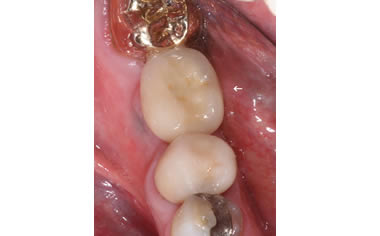

More back teeth replaced by dental implants

Case Four (4 images)

Case Five (4 images)